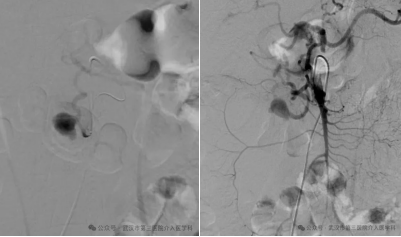

精准导航:在DSA透视的引导下,我们像“巡航导弹”一样,将一根细长而柔软的导管,从股动脉一路精准地“行驶”到肠系膜上动脉,最终抵达破裂的动脉瘤分支。

封堵“决堤口”:通过导管,我们向破裂的动脉瘤及其两端释放了数枚微小的 “弹簧圈” 。这些弹簧圈会迅速在破口处盘绕成团,形成一个致密的“塞子”,瞬间堵死破口,让血液无法再流出。

手术成功了! 屏幕上显示,破裂的血管不再造影剂外溢。这意味着,“决堤口”被成功封堵。整个过程,患者体表只有一个针眼大小的伤口。术后,王先生的血压很快稳定下来,脱离了生命危险。